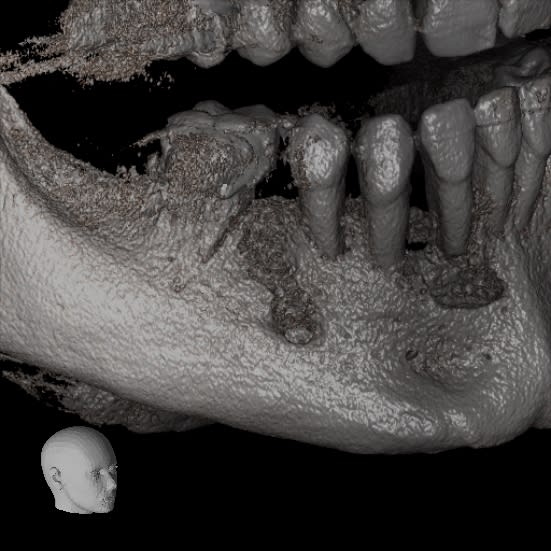

je viens de tomber sur une clé usb avec quelques images...

Guenfra i5kyps - Eugenol

Xyzview 20140607 112446 ida9qe - Eugenol

Xyzview 20140703 133108 osyuum - Eugenol

Volumerenderer 20140703 1331 wcokhm - Eugenol

Xyzview 20140619 122545 wt8h7c - Eugenol